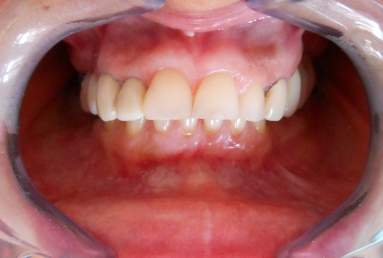

After treatment:

– zirconium/ceramic bridge in the lateral right maxillary area

– two implants and zirconium/ceramic bridge in the lateral left maxillary area

– full ceramic individual crowns in the frontal maxillary area, correcting at the same time the occlusion and the position of the frontal teeth.

– the lower arch was restored with a zirconium/ceramic bridge in the lateral right area and composite esthetic fillings + teeth whitening for the rest of the natural teeth.